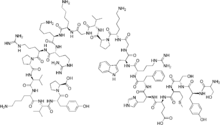

| Formula | C207H308N56O58S |

| Molar mass | 4541.14 g·mol−1 |

| Other names | Ba 30920 α1–24 corticotrophin Ser-Tyr-Ser-Met-Glu-His-Phe-Arg-Trp-Gly-Lys-Pro-Val-Gly-Lys-Lys-Arg-Arg-Pro-Val-Lys-Val-Tyr-Pro |

| Formula | C136H210N40O31S |

| Molar mass | 2933.49 g·mol−1 |

The form that is made synthetically is tetracosactide, also known as synacthen,[4] tetracosactrin and cosyntropin.[2]: 1165 [3]: 271 [5] It consists of the first 24 (of a total of 39) amino acids of ACTH and retains full function of the parent peptide.[2]: 1165 Tetracosactide stimulates the release of corticosteroids such as cortisol from the adrenal glands, and is used for the ACTH stimulation test to assess adrenal gland function.[3]: 271

The synthetic form consists of the first 24 (of a total of 39) amino acids of ACTH and retains full function of the parent peptide.[2]: 1165